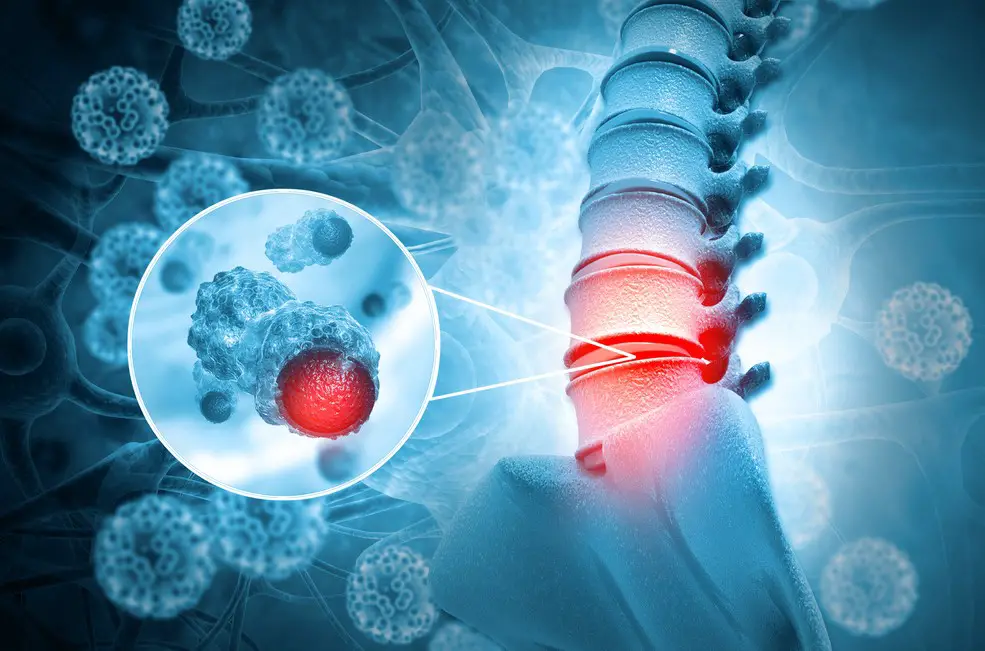

Bệnh u tủy sống là tình trạng tủy sống xuất hiện những khối u gây chèn dây thần kinh vào các cấu trúc thần kinh trong ống sống. Khi khối u phát triển to lên, chúng sẽ gây chèn ép vào tủy sống dẫn đến sự thiếu hụt về thần kinh ở đoạn tủy sống phía dưới. Bài viết sau sẽ cung cấp thông tin những điều cần biết về bệnh u tủy sống.

U tủy sống là tình trạng có những khối u phát triển trong tủy sống hoặc ở màng cứng (lớp phủ bên ngoài tủy sống). Các khối u tủy sống có thể bao gồm:

- Khối u nội tủy, xuất phát từ các tế bào nằm bên trong tủy sống. Ví dụ như u tế bào hình sao, u thần kinh đệm,…

- Khối u ngoài tủy, dưới màng cứng phủ bên ngoài tủy hoặc nằm tại các rễ thần kinh vươn ra khỏi tủy sống. Các khối u này tuy nằm bên ngoài tủy nhưng vẫn có thể tạo áp lực chèn lên tủy và ảnh hưởng đến chức năng của tủy sống. Ví dụ như u vỏ bọc thần kinh, u sợi thần kinh, u màng não,…

Và cho dù khối u nằm bên trong tủy hay nằm ngoài tủy, khối u vừa mới phát triển hay khối u di căn từ các khối u khác thì cũng có thể dẫn đến các vấn đề về thần kinh, gây tàn tật vĩnh viễn hoặc thậm chí đe dọa tính mạng người bệnh.